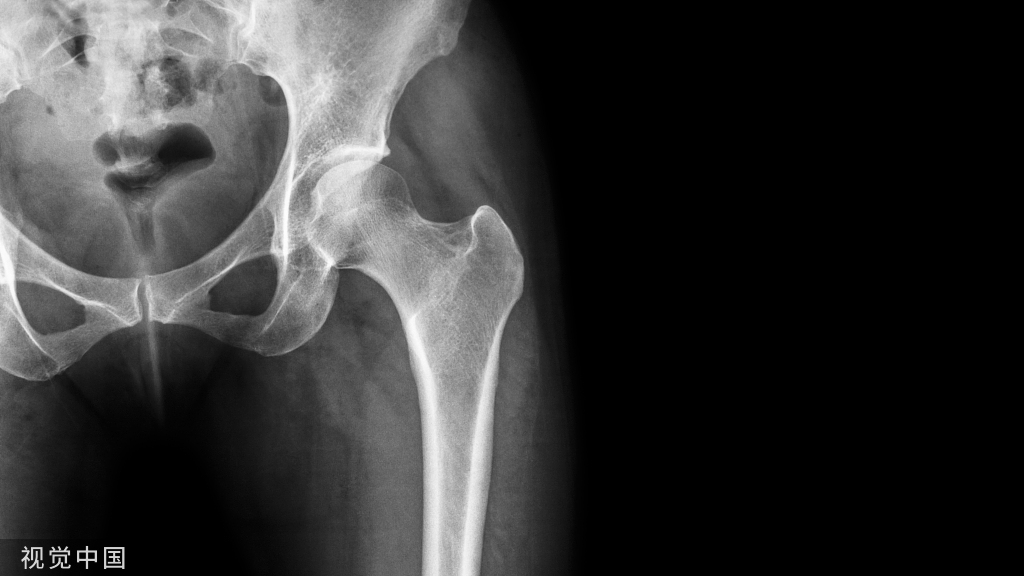

• 股骨近端骨折禁止应用钢板

此处应用钢板有两种情况一是不会使用髓内固定,设备条件达不到;再就是理念落后见的病例少,交流少。此处外侧全部是长应力,钢板为张力钢板,内收肌力量强大,目前的钢板不能承受反复的弯曲应力,金属疲劳断裂失败率高,以下病例切开,钢丝捆绑进一步骨膜剥离,破坏了原始血肿,干扰骨愈合,都是失败原因